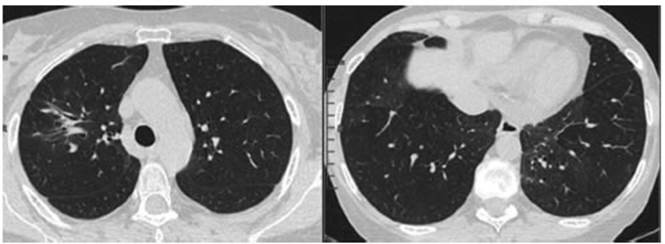

resolution and improved tomographic images after two months of treatment. CT 03/8/2022

(Figure 3): marked size reduction of consolidation in the right corner and

disappearance of the other infiltrates in lung parenchyma.